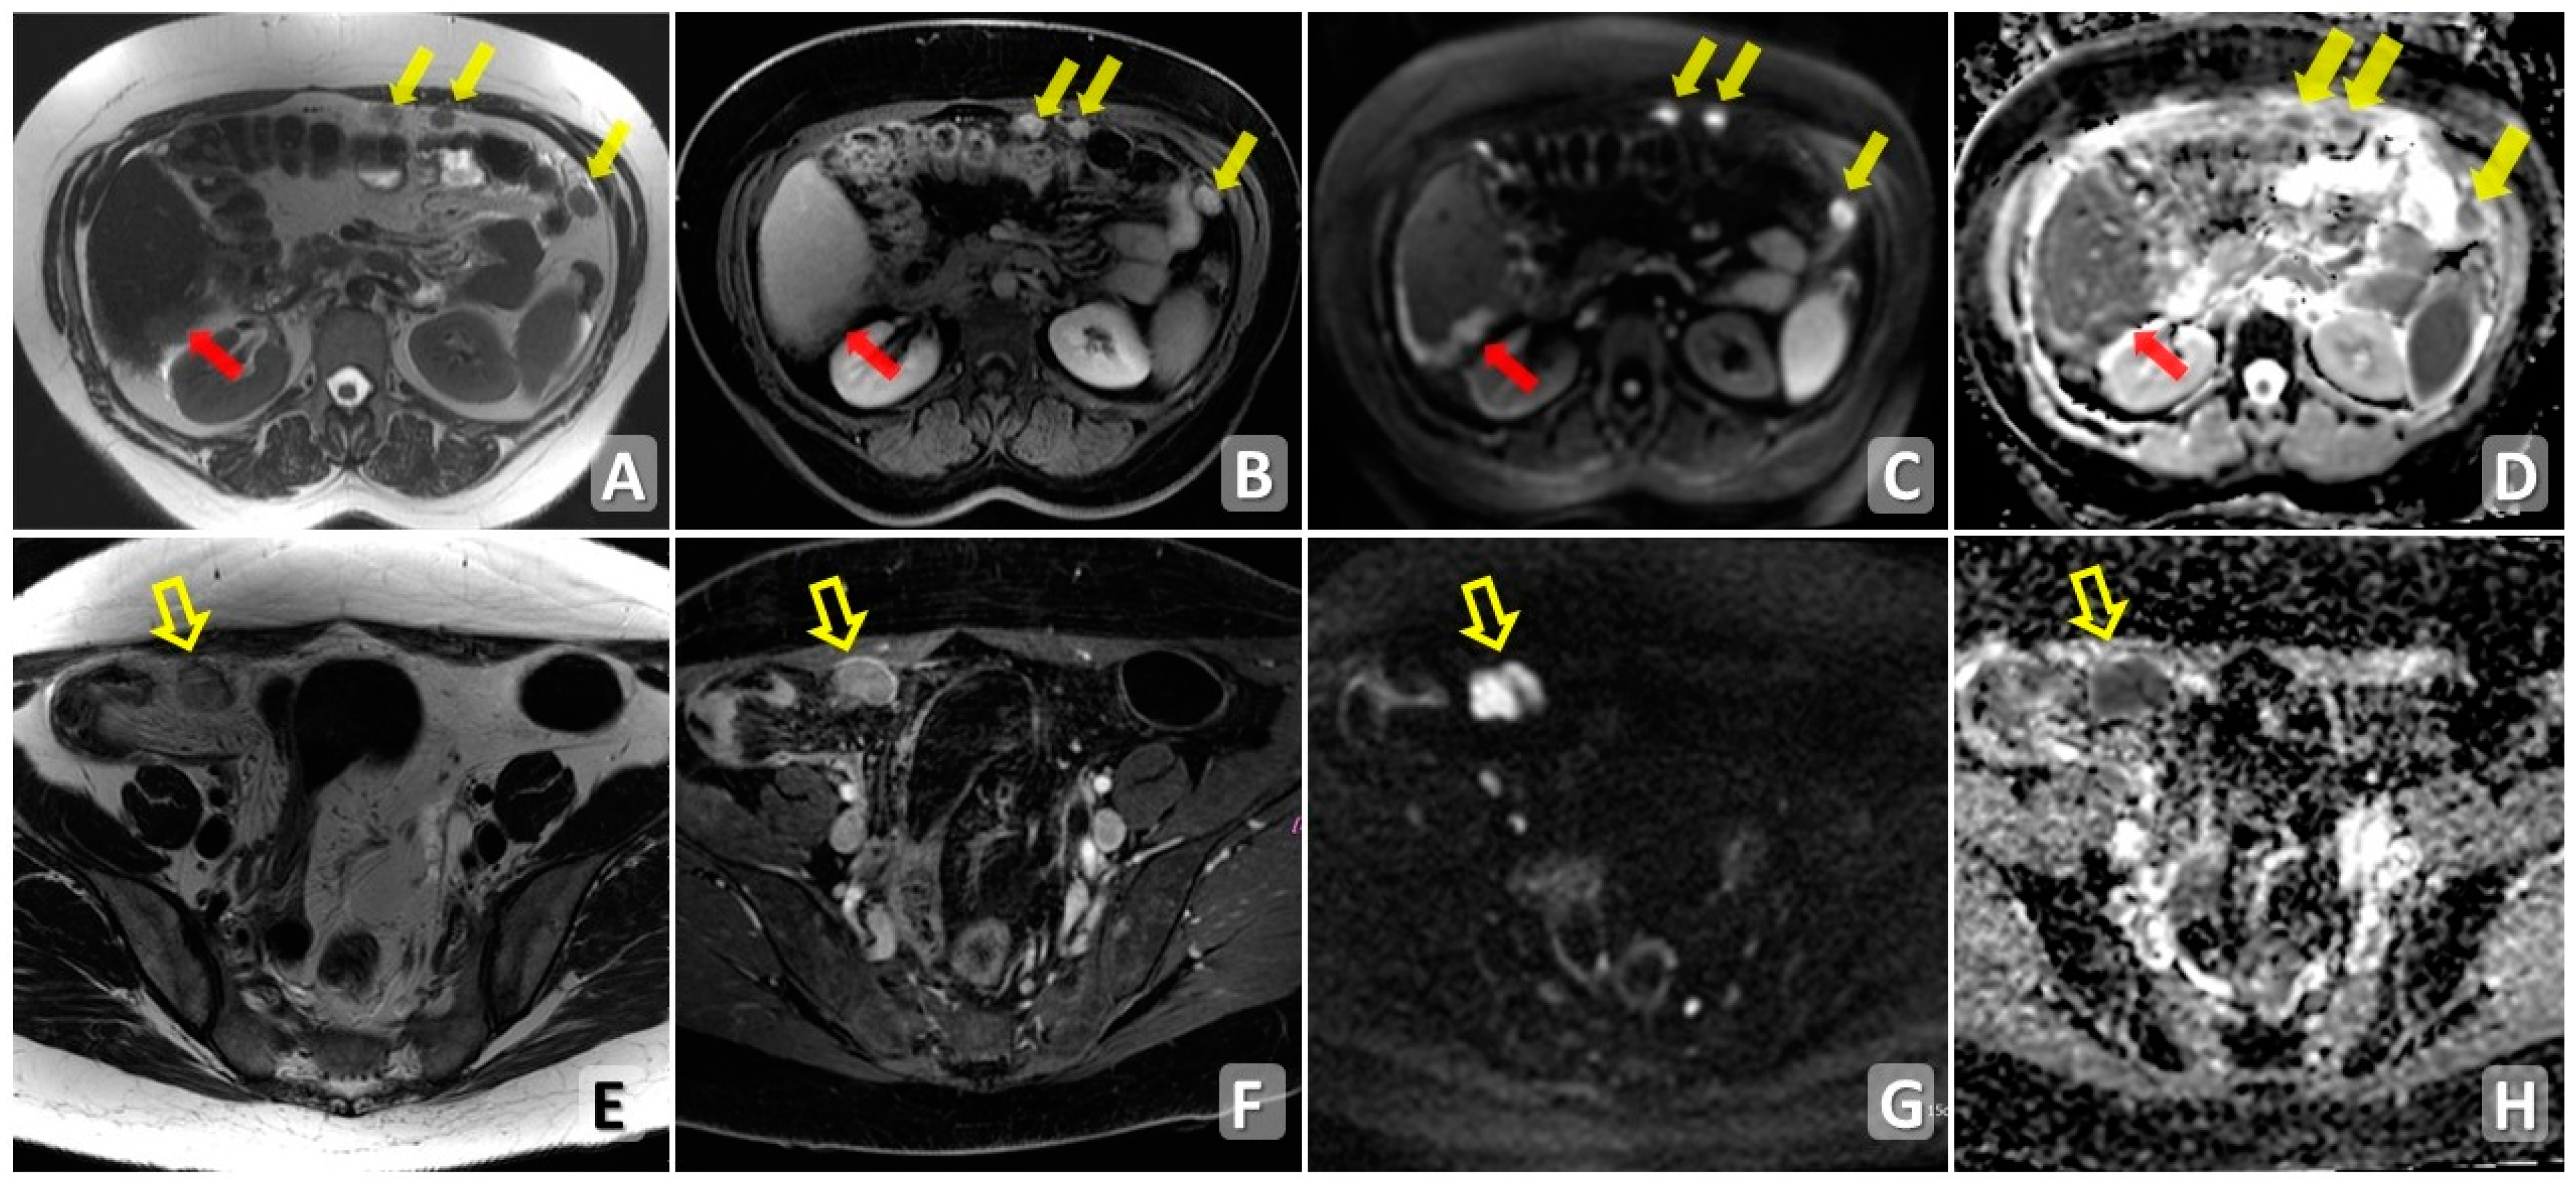

4.2. Magnetic Resonance Imaging

5. Diffusion Pathways

6. Disease Patterns

7. Scoring System in Diagnostic Imaging